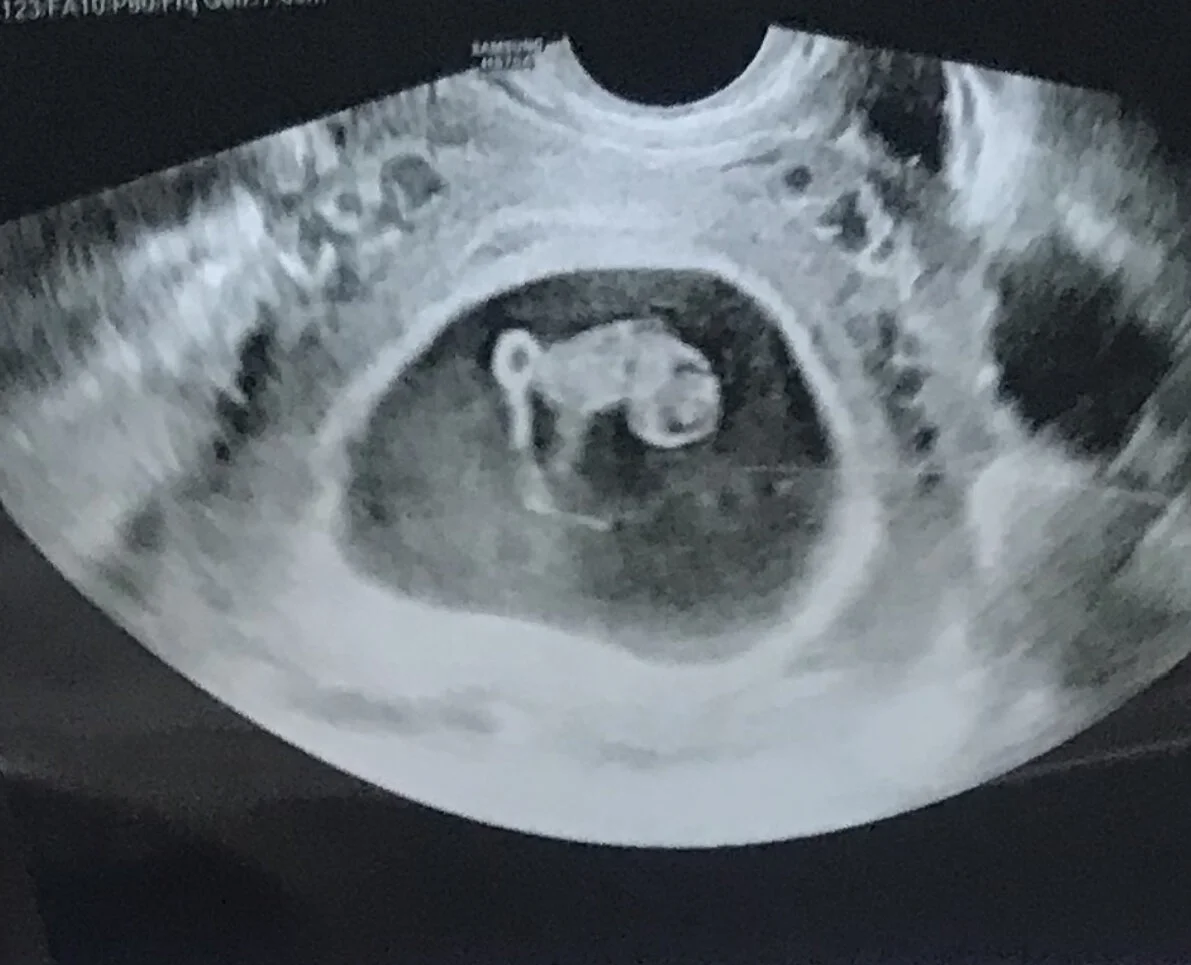

“A substance of things hoped for evidence of things not seen” Hebrews 11:1 describes faith. But this is exactly how I describe “motherhood.”